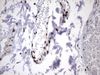

Applications IHC, WB

Recommended Dilution WB 1:2000, IHC 1:150